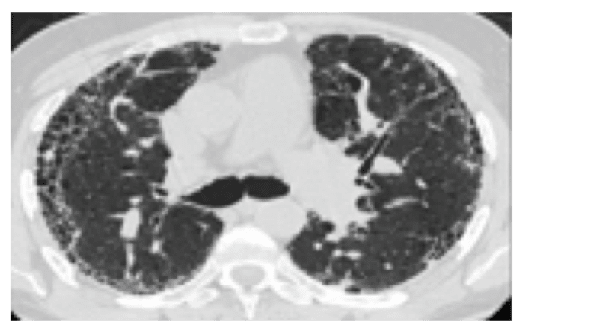

Op haar meest recente HRCT-scan zijn afwijkingen gevonden:

• subpleurale sparing

• bilateraal matglas met reticulaties

Deze kenmerken passen bij een radiologisch NSIP-patroon, wat vaak voorkomt bij patiënten met SSc-ILD.